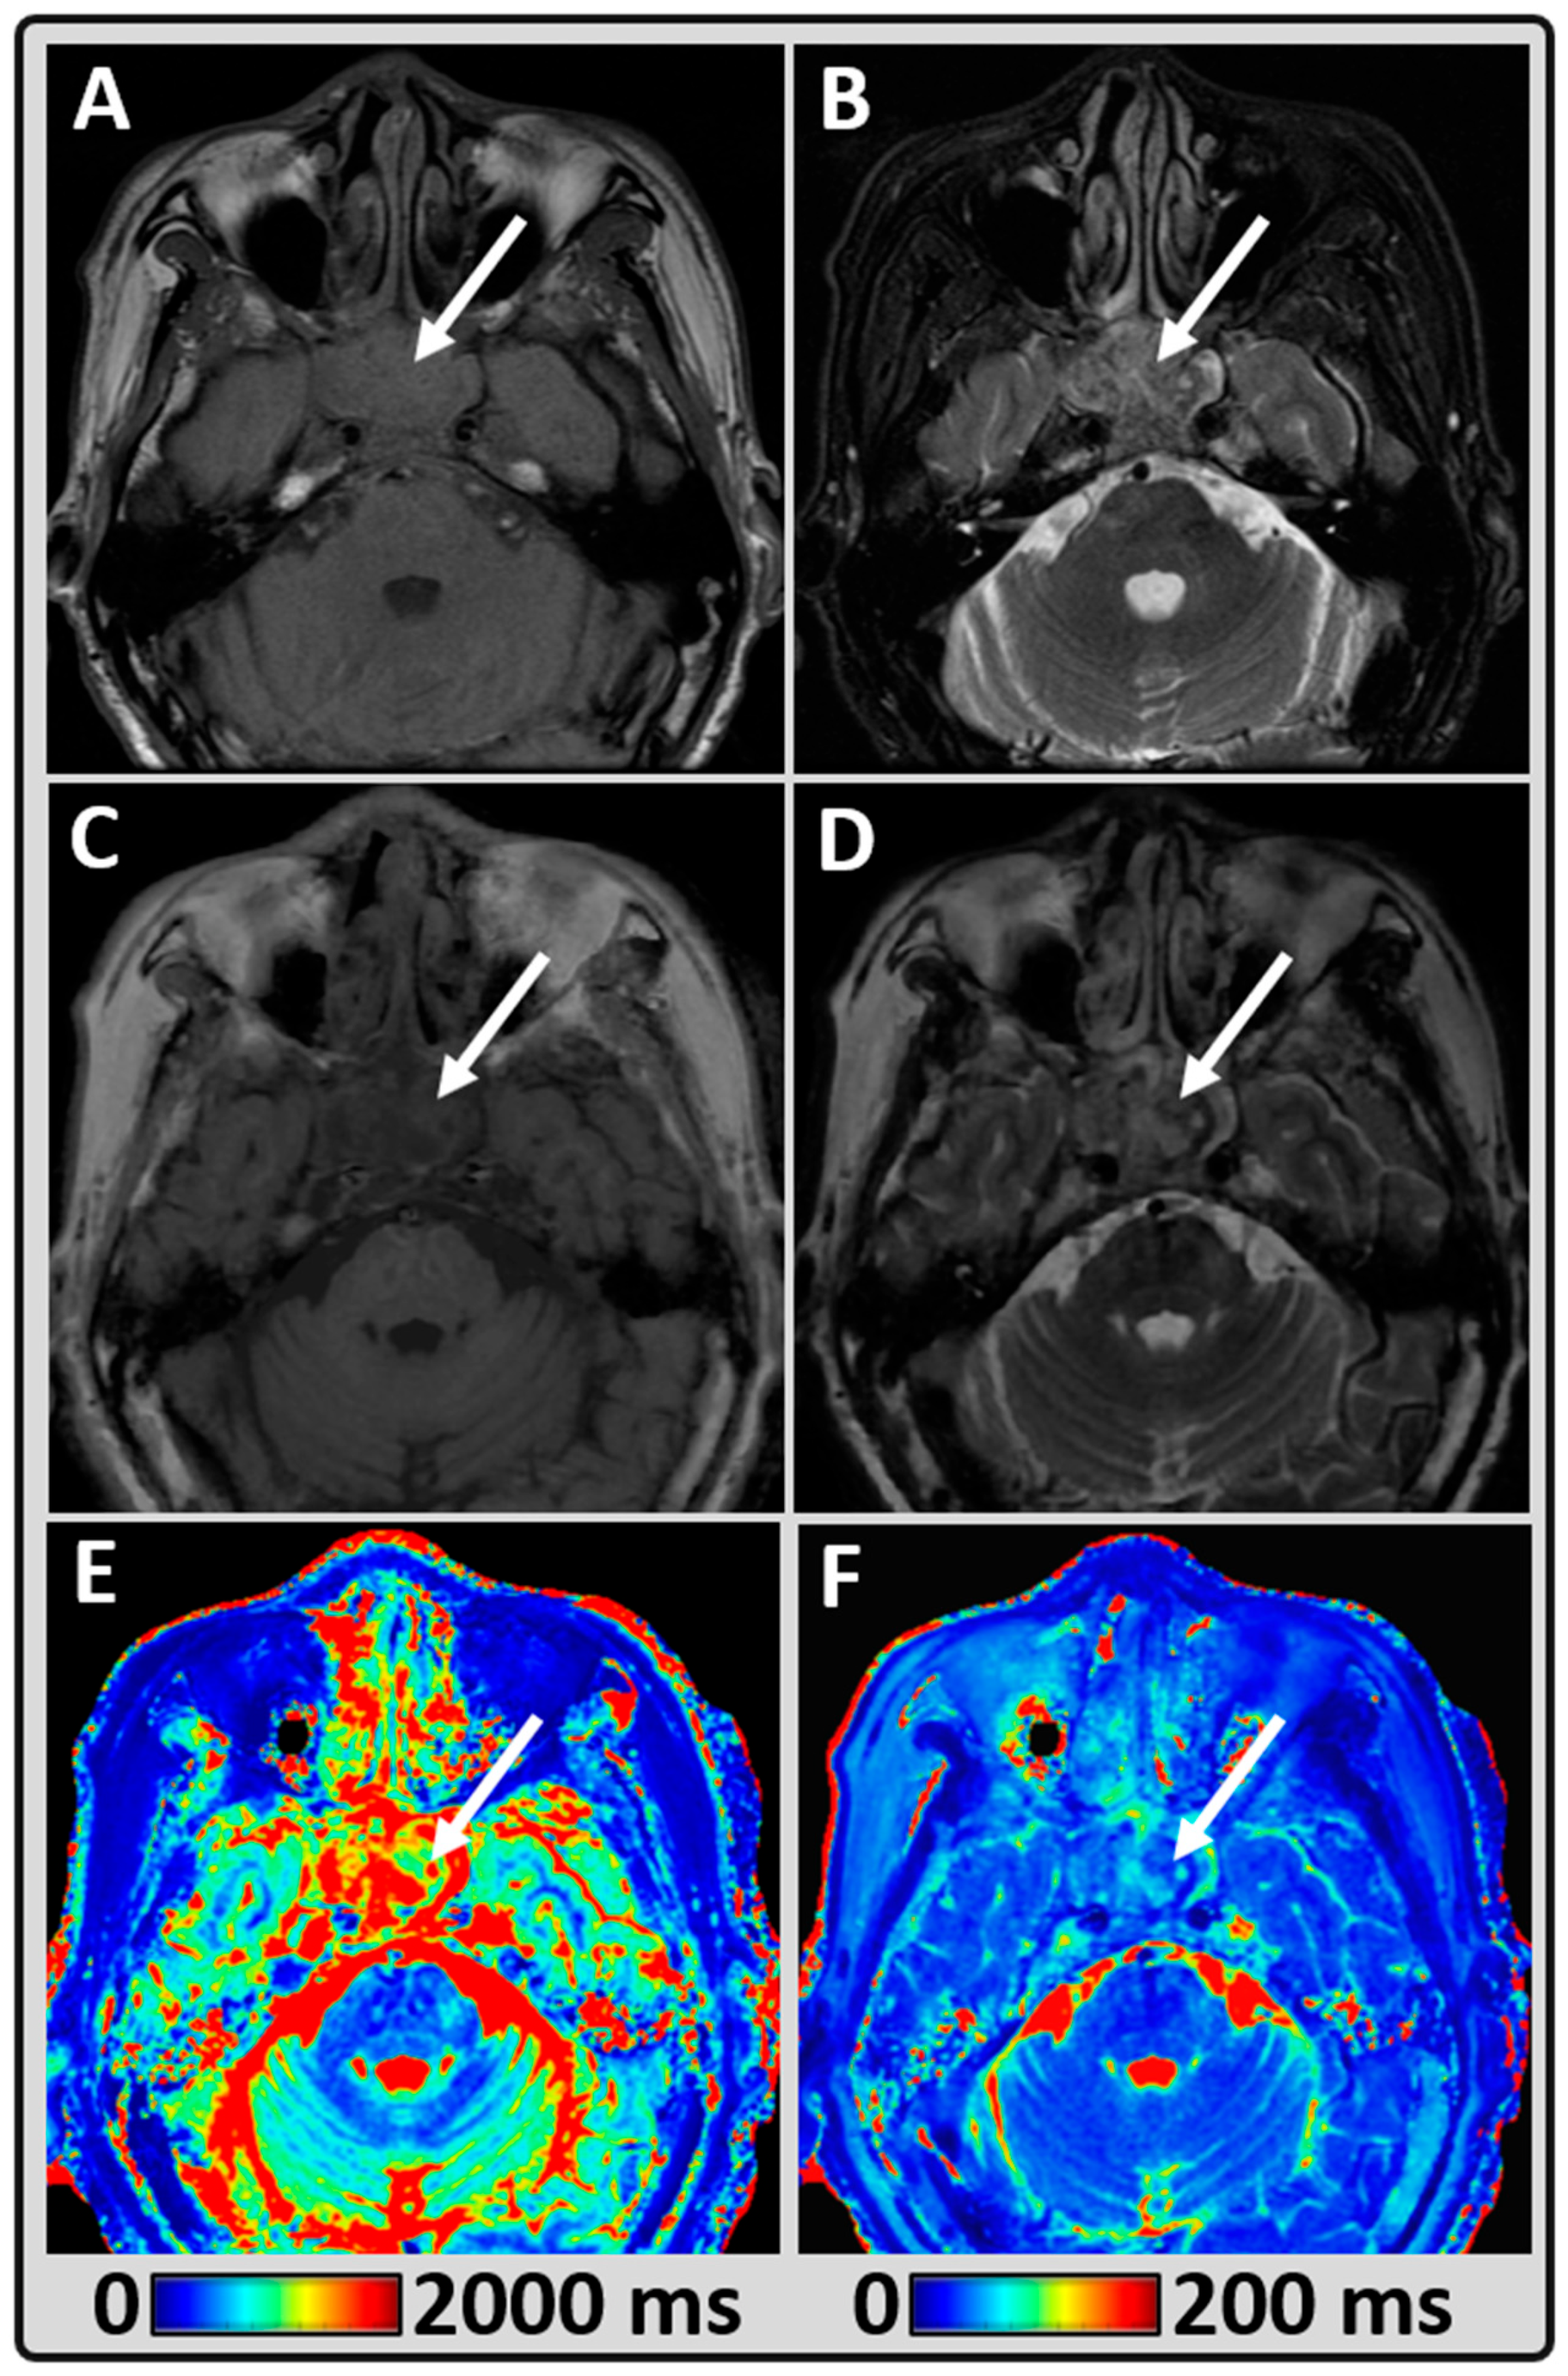

2.2. MRI Data Acquisition

2.3. Standard Head and Neck Imaging

2.4. Synthetic MR Imaging (MAGiC)

2.5. MRI Data Processing